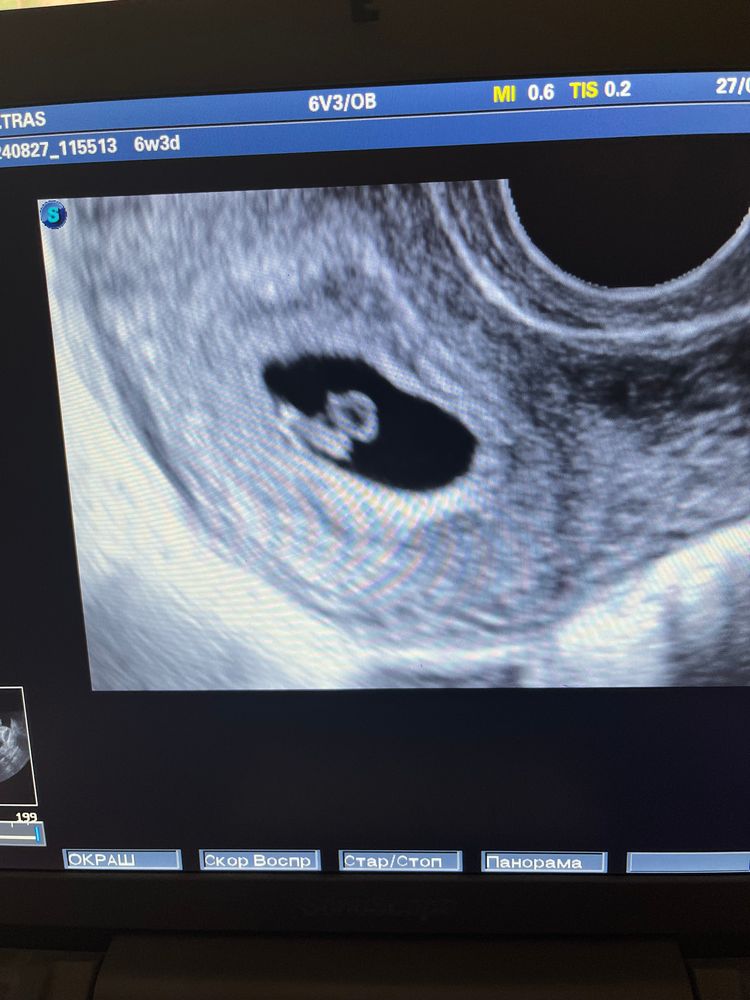

Сегодня нас нашли❤️

Мария, Спасибо 🫶Нас нашли ещё раз сегодня))) но пока сб нет, через две недели пойдем опять.🫣

поздравляю, отличная крошечка) растите крепкими !

Ктг на сроке 39 и 2 дня Г Иваново врач УЗИ